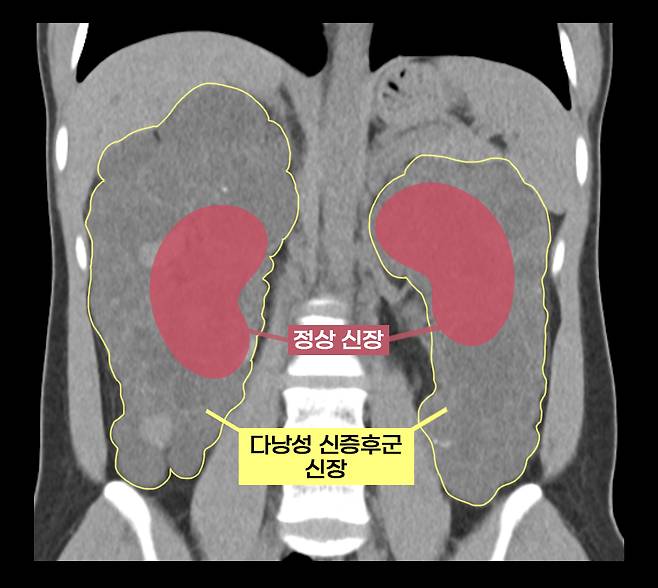

이 씨는 상염색체 우성 다낭성 신증후군을 앓았다. 다낭성 신증후군은 신장에 셀 수없이 많은 낭종이 발생해 신장이 최대 축구공만큼 커지는 유전 질환이다. 1,000명 중 한 명꼴로 비교적 흔하게 발생하며 대부분 만성 신부전으로 이어진다.

보통의 만성 신부전 환자는 신장이식을 할 때 기존 신장을 그대로 두지만, 다낭성 신증후군 환자는 기존 신장을 떼어내야 한다. 이미 신장이 비대해진 상태이므로 새로운 신장이 들어올 공간을 확보해야 할 뿐만 아니라, 낭종 감염과 낭종 파열로 인한 출혈, 신장암 발병 등의 합병증 위험이 있어 양측 신장을 제거하고 신장이식을 진행한다.